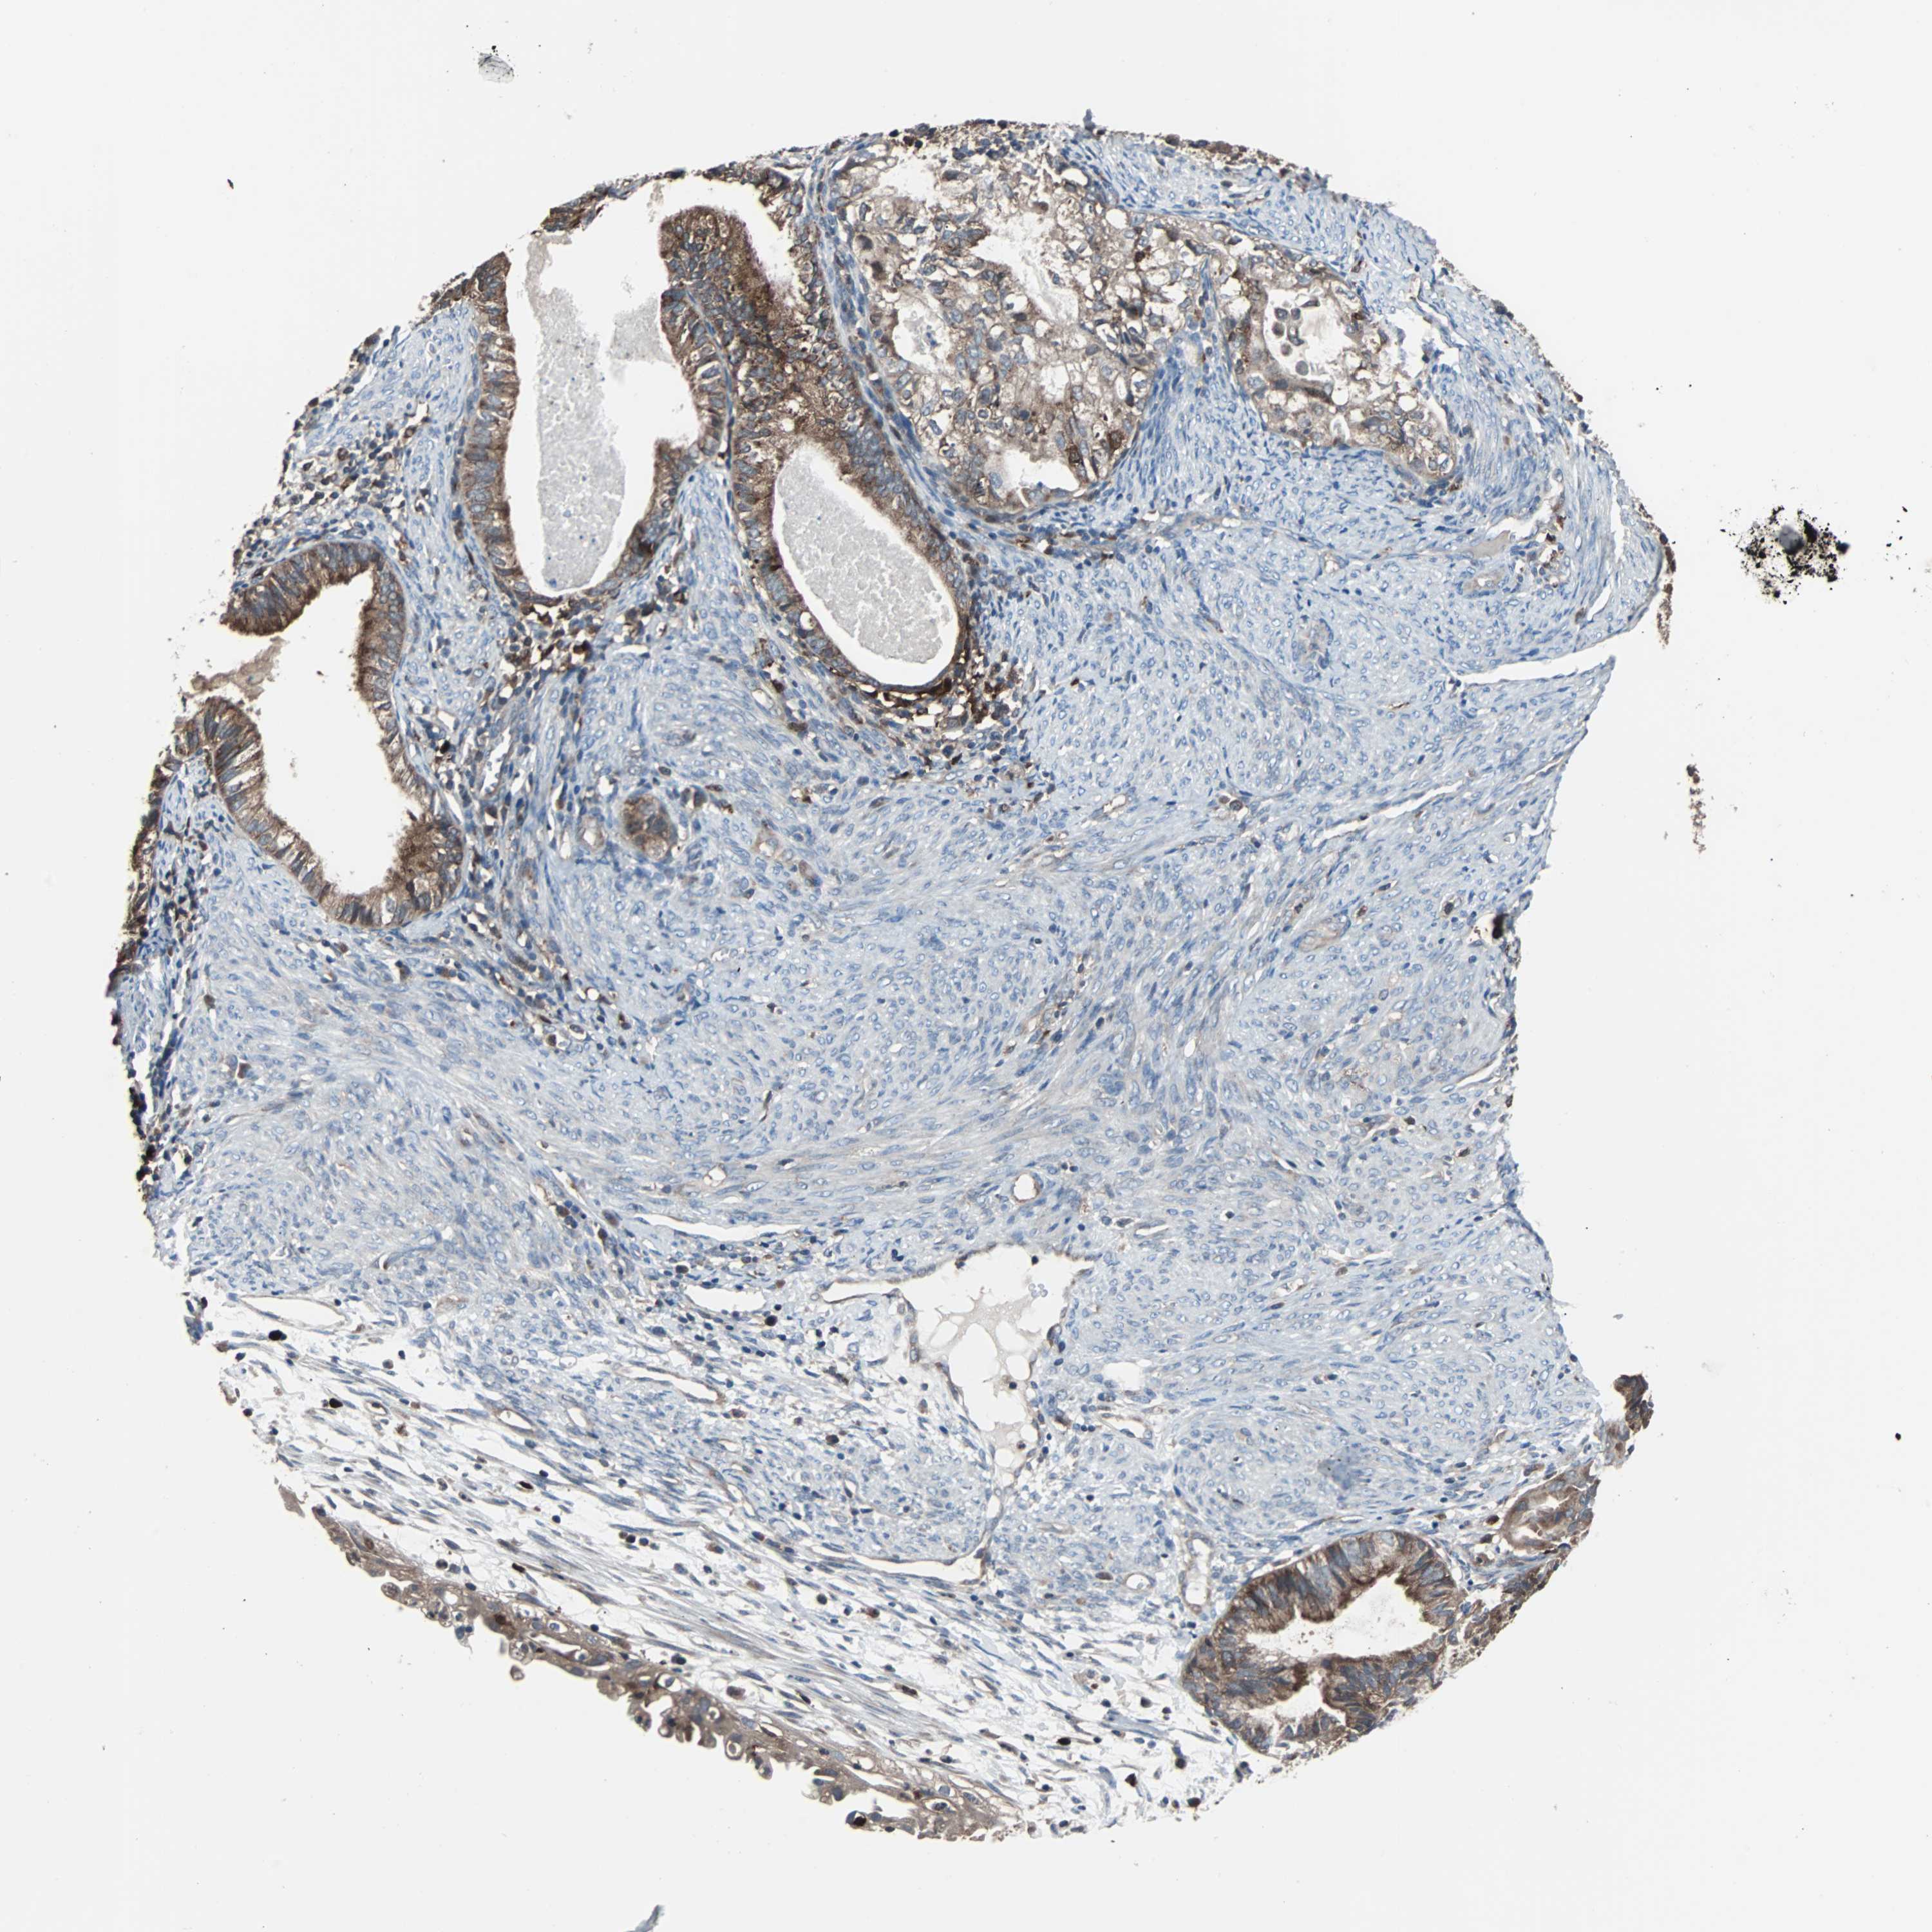

CERVICAL CANCER - Protein expressioni

A mouse-over function shows sample information and annotation data. Click on an image to view it in a full screen mode. Samples can be filtered based on level of antibody staining by selecting one or several of the following categories: high, medium, low and not detected. The assay and annotation is described here.

Note that samples used for immunohistochemistry by the Human Protein Atlas do not correspond to samples in the TCGA dataset.

Antibody stainingi

Antibody staining in the annotated cell types in the current human tissue is reported as not detected, low, medium, or high, based on conventional immunohistochemistry profiling in selected tissues. This score is based on the combination of the staining intensity and fraction of stained cells.

Each image is clickable and will lead to virtual microscopy that enables deeper exploration of all samples and also displays staining intensity scores, fraction scores and subcellular localization as well as patient and tissue information for each sample.

Antibody HPA003565

Antibody CAB005312

Staining

High

Medium

Low

Not detected

Intensity

Strong

Moderate

Weak

Negative

Quantity

>75%

75%-25%

<25%

None

Location

Nuclear

Cytoplasmic/membranous

Cytoplasmic/membranous,nuclear

Squamous cell carcinoma, NOS

Adenocarcinoma, NOS